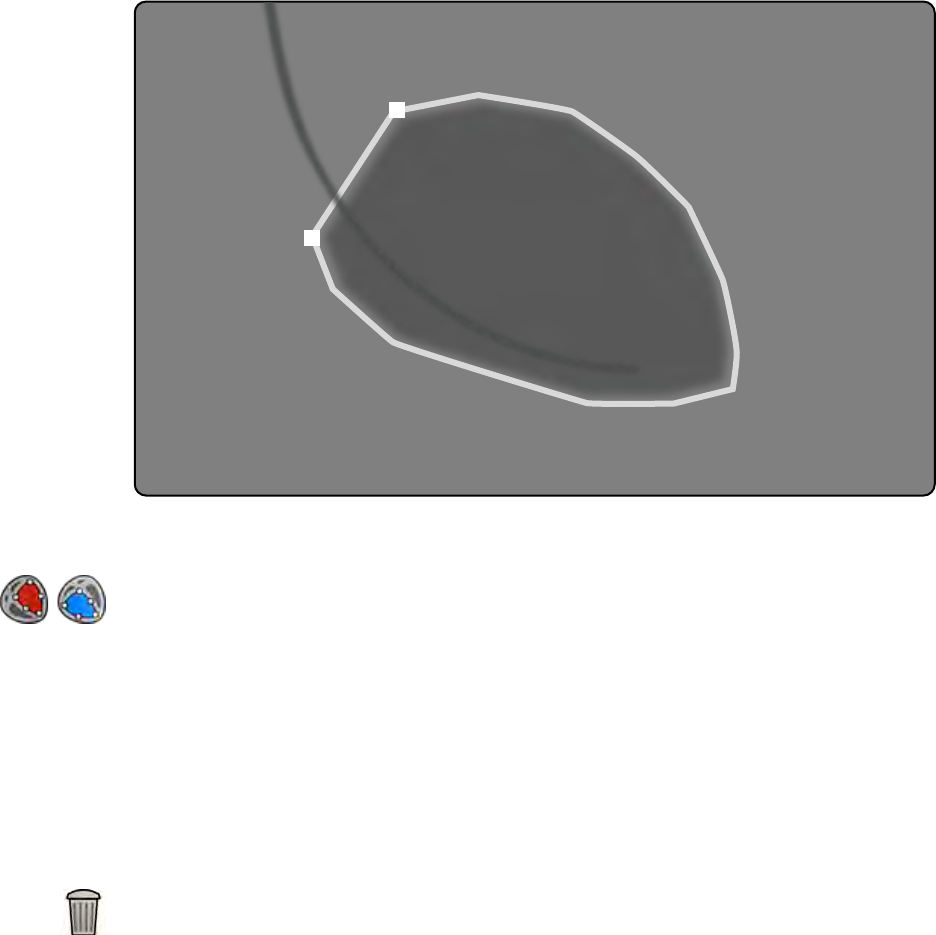

Cere-

bral

(Mózg)

Cere-

bral

(Mózg)

2 fps